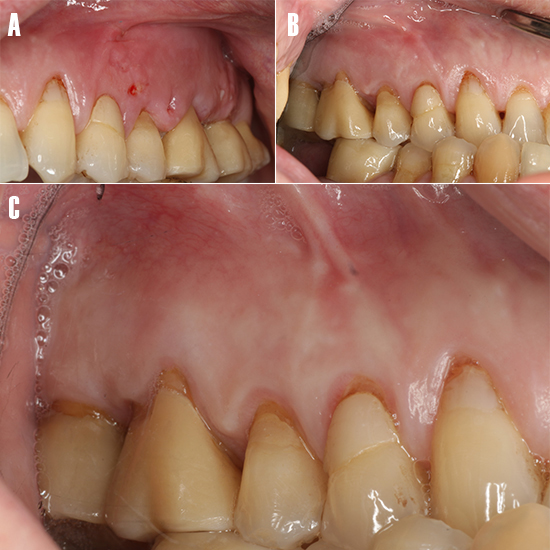

Resultado clínico

La sutura se removió una semana después de la cirugía. Se pudo observar como la tumefacción de los tejidos blandos remitió (Fig. 7A). El paciente fue citado 4 semanas tras la cirugía para monitorizar la sintomatología clínica y evaluar la zona tratada (Fig. 7B). A los 12 meses se reevaluó el caso (Fig. 7C) y se realizó una TCHC para valorar el seno maxilar afectado, se pudo observar como la cicatrización de la periodontitis apical y la patología sinusal remitieron (Fig. 8).

Figura 7. Evolución clínica tras la cirugía. A) Tejidos blandos tras el retiro de puntos a los 7 días, observándose cierta inflamación. B) A los 30 días, se aprecia que la inflamación ha remitido en su totalidad. C) Estado periodontal a los 12 meses.